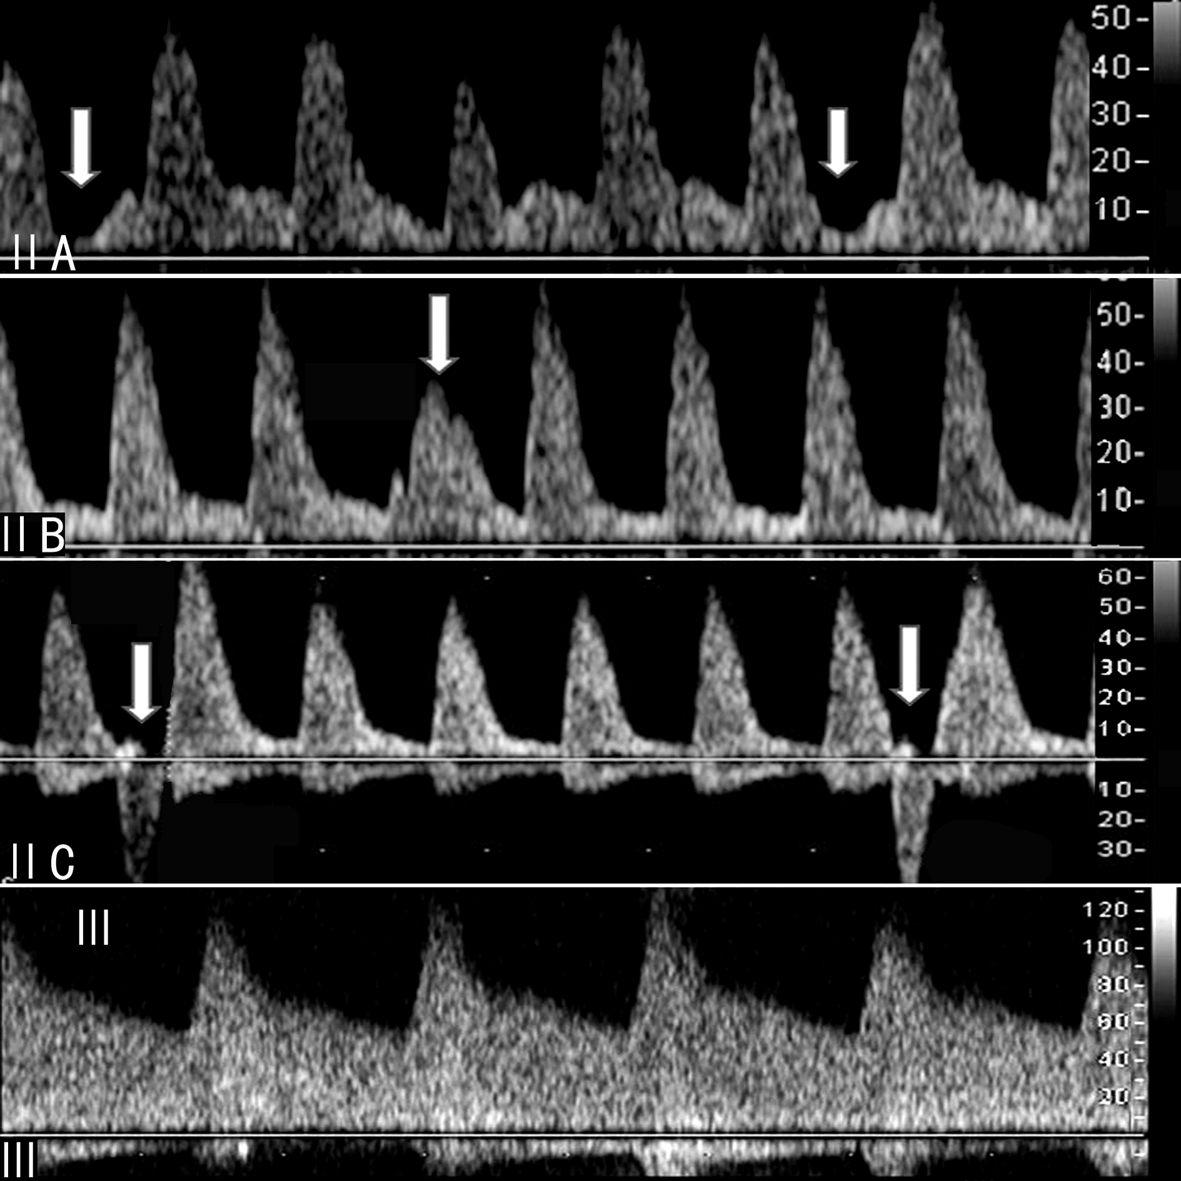

Sushil等将MCA频谱分为Ⅰ、Ⅱ、Ⅲ三种类型,其中Ⅰ型和Ⅱ型又分为A、B、C亚型(图2,3)。不同类型的MCA频谱具有不同的临床意义。

图2胎儿MCA多普勒血流速度曲线分型

图3胎儿MCA多普勒血流速度曲线亚型